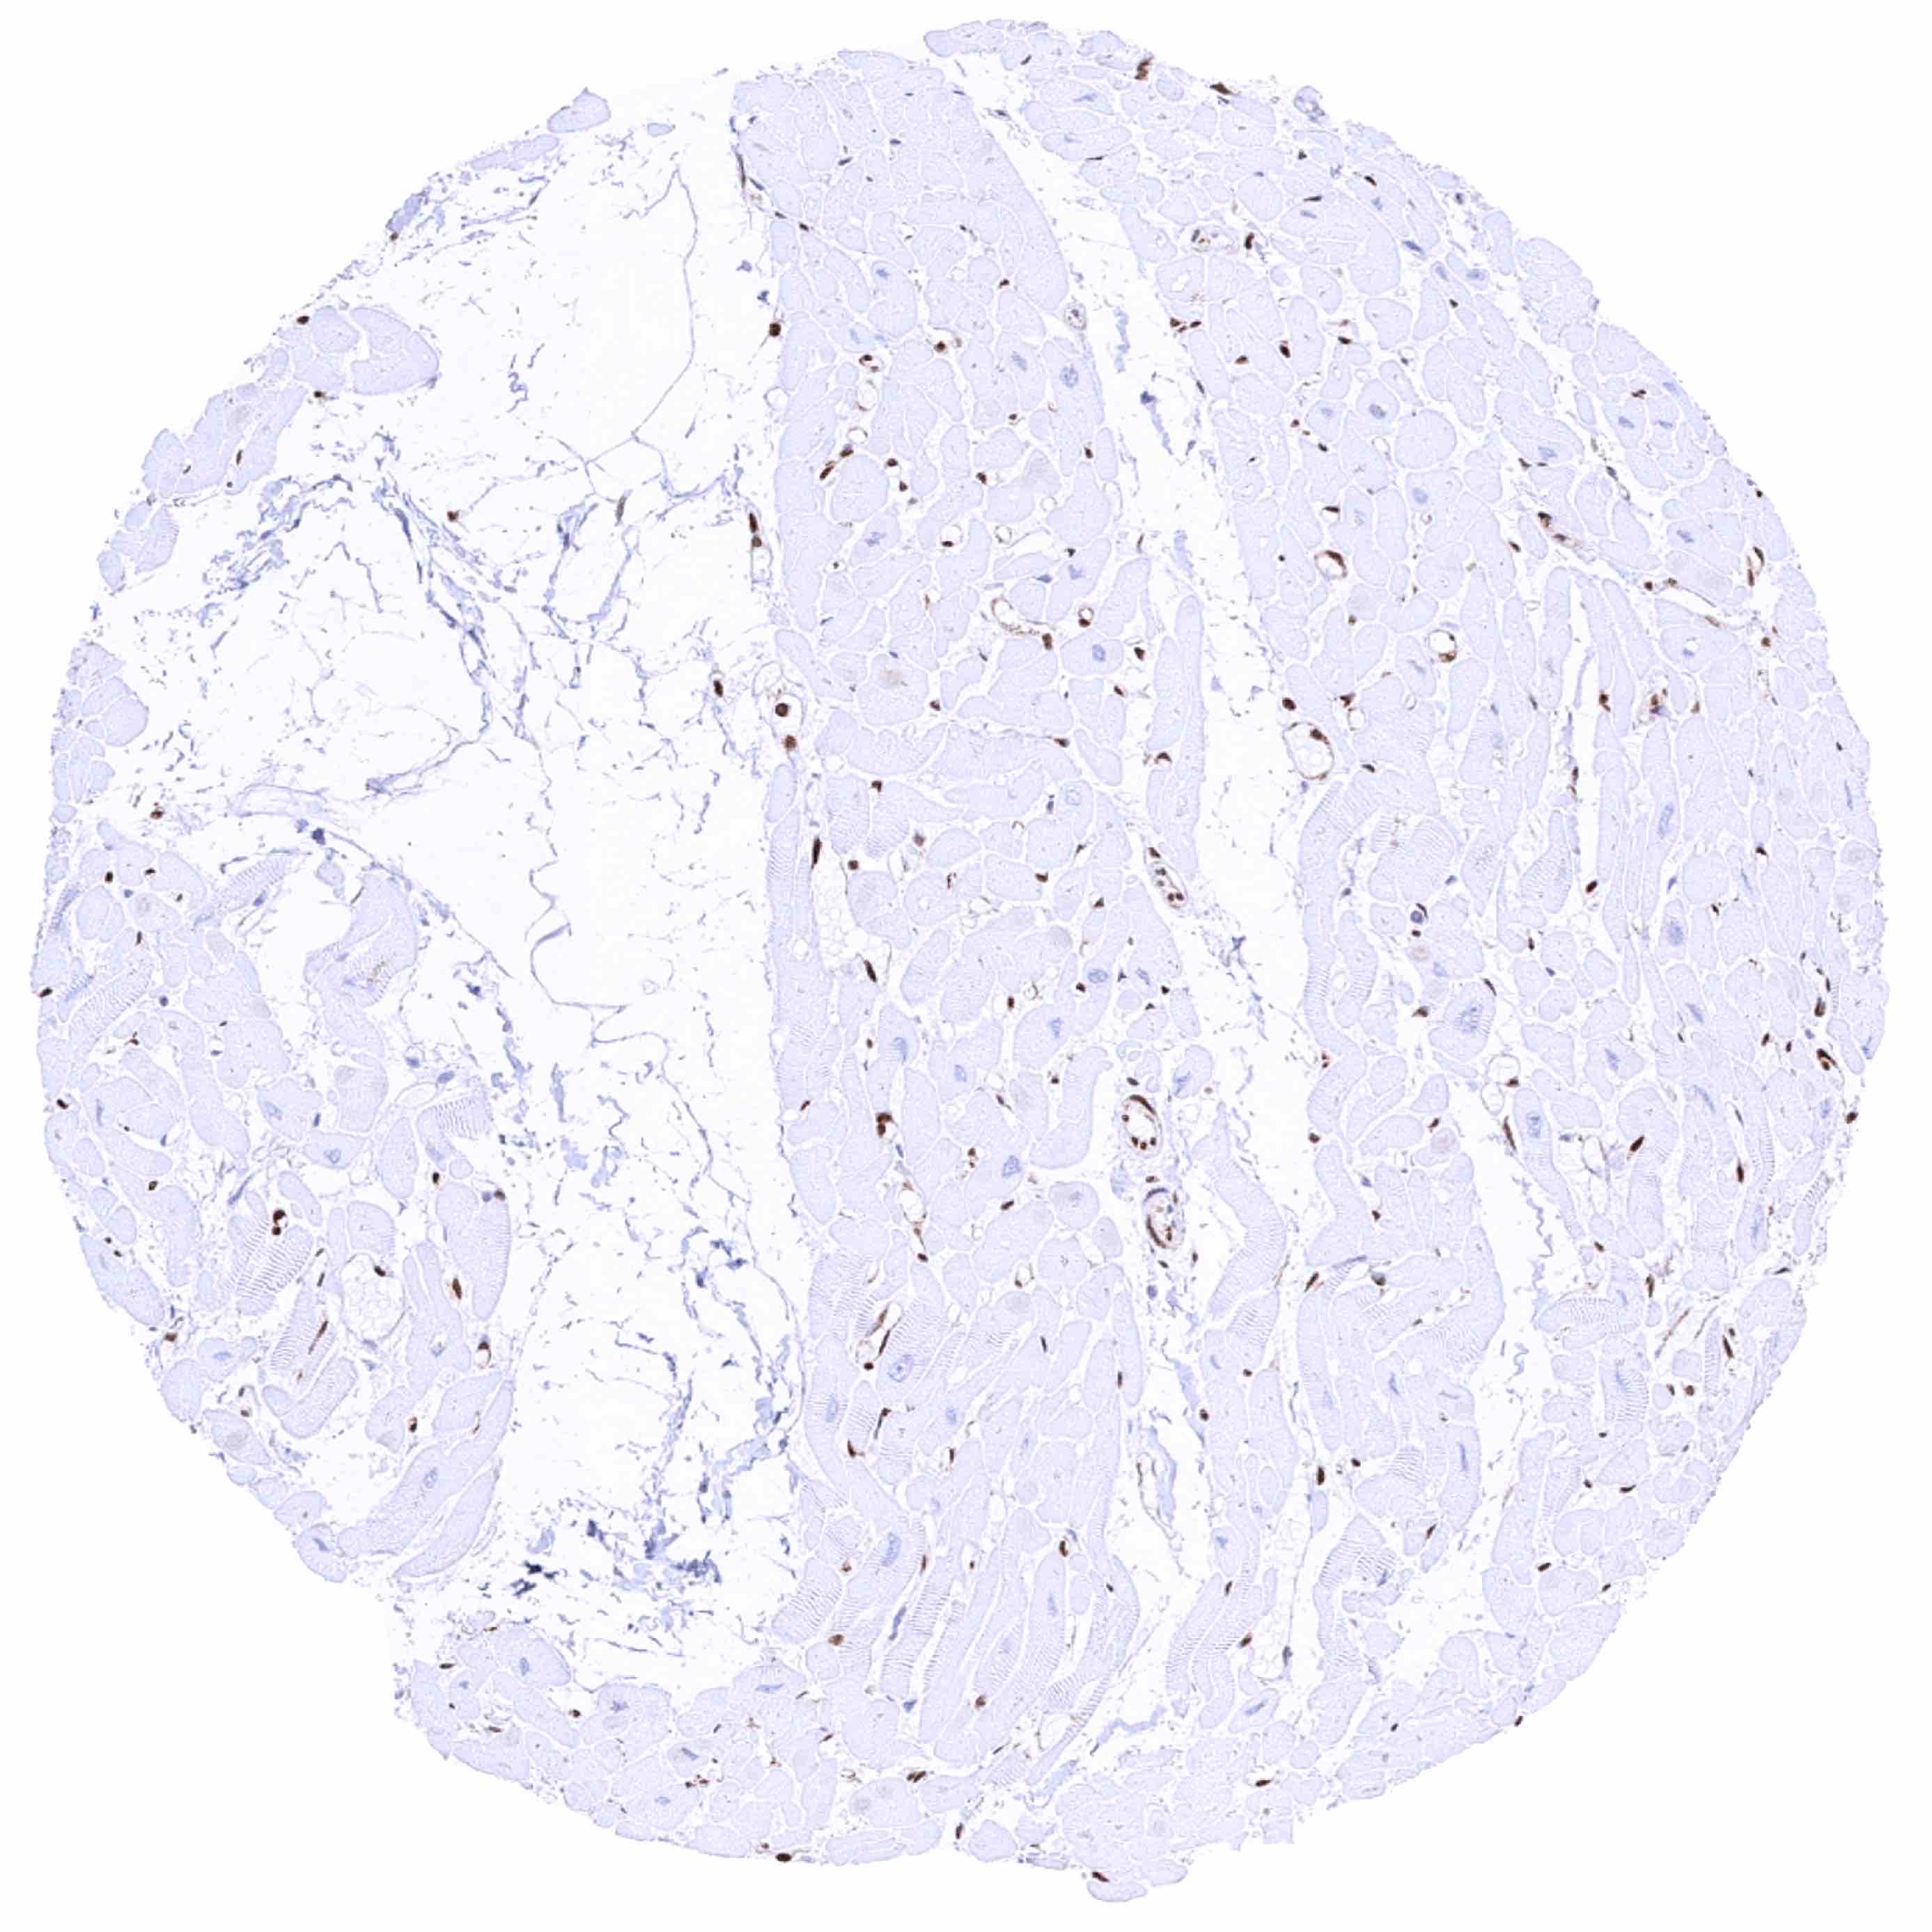

Skeletal muscle